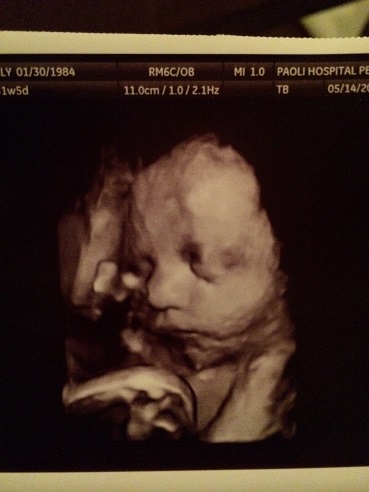

Week 32 – Sonogram

Kelly had a follow up sonogram on Wednesday to make sure everything was where it was supposed to be. Piglet is weighing in at 4 pounds and 2 ounces. The pregnancy app says it should be 3.75 pounds, so he’s a little above average. The nurse said the baby was in the 54% percentile for height and weight, so she said everything looks great and Kelly was cleared for a regular delivery. We got another 3D ultrasound and got to see his face. We also got to see him move his arms and make some funny faces. This was the best picture we got, he kind of looks like me. Kelly disagrees and says he has her lips. I don’t see it.